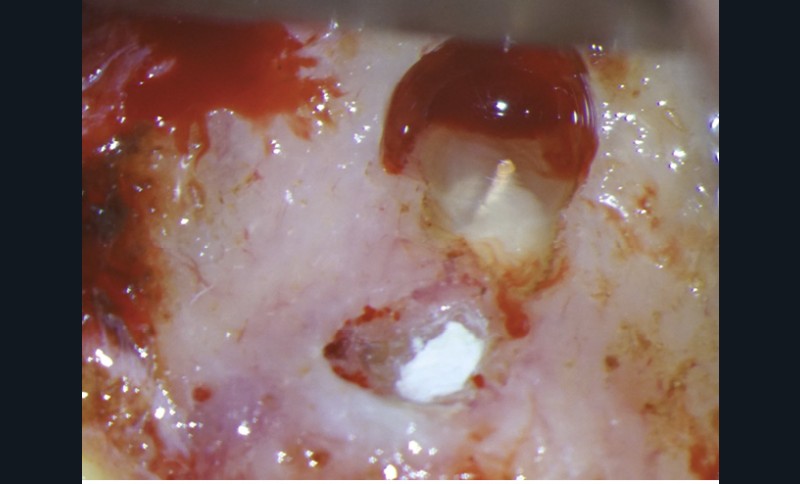

Le laser Er:YAG va permettre une élimination des débris en surface, une stérilisation, avec comme irrigation de l’eau stérile [36] et en coupant le spray, une hémostase avec la formation d’une couche de coagulation [37] propre à la formation d’un pont dentinaire au contact du biomatériau, qui peut être bio-actif, tel que la Biodentine (Septodont) (fig. 6a à d).

Protocole opératoire : sous anesthésie, une cavité suffisante à recevoir le biomatériau (2 à 3 mm) sous champ opératoire est réalisée. La désinfection au laser Er:YAG (40 mJ ; 20 Hz) sous spray, pendant 20 secondes, est alors mise en œuvre. S’en suit éventuellement une coagulation de 3 secondes, en coupant le spray, puis la mise en place du biomatériau Biodentine (Septodont). Il sera ensuite recouvert d’un matériau de restauration adéquate.